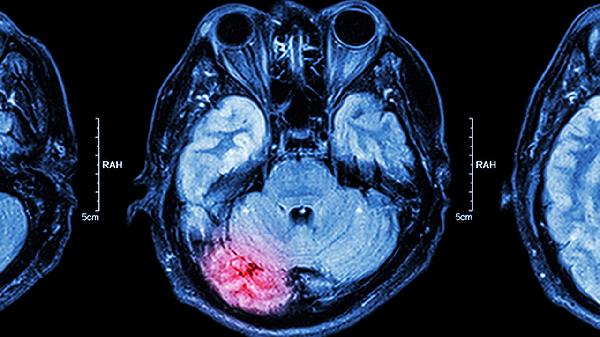

对于药物治疗无效或存在鼻窦解剖结构异常的患者,可考虑鼻内镜下筛窦开放术、鼻窦球囊扩张术等手术方式。手术能解除窦口阻塞并改善引流,术后需定期冲洗鼻腔防止粘连。伴有严重并发症如颅内感染时,可能需要联合神经外科干预。